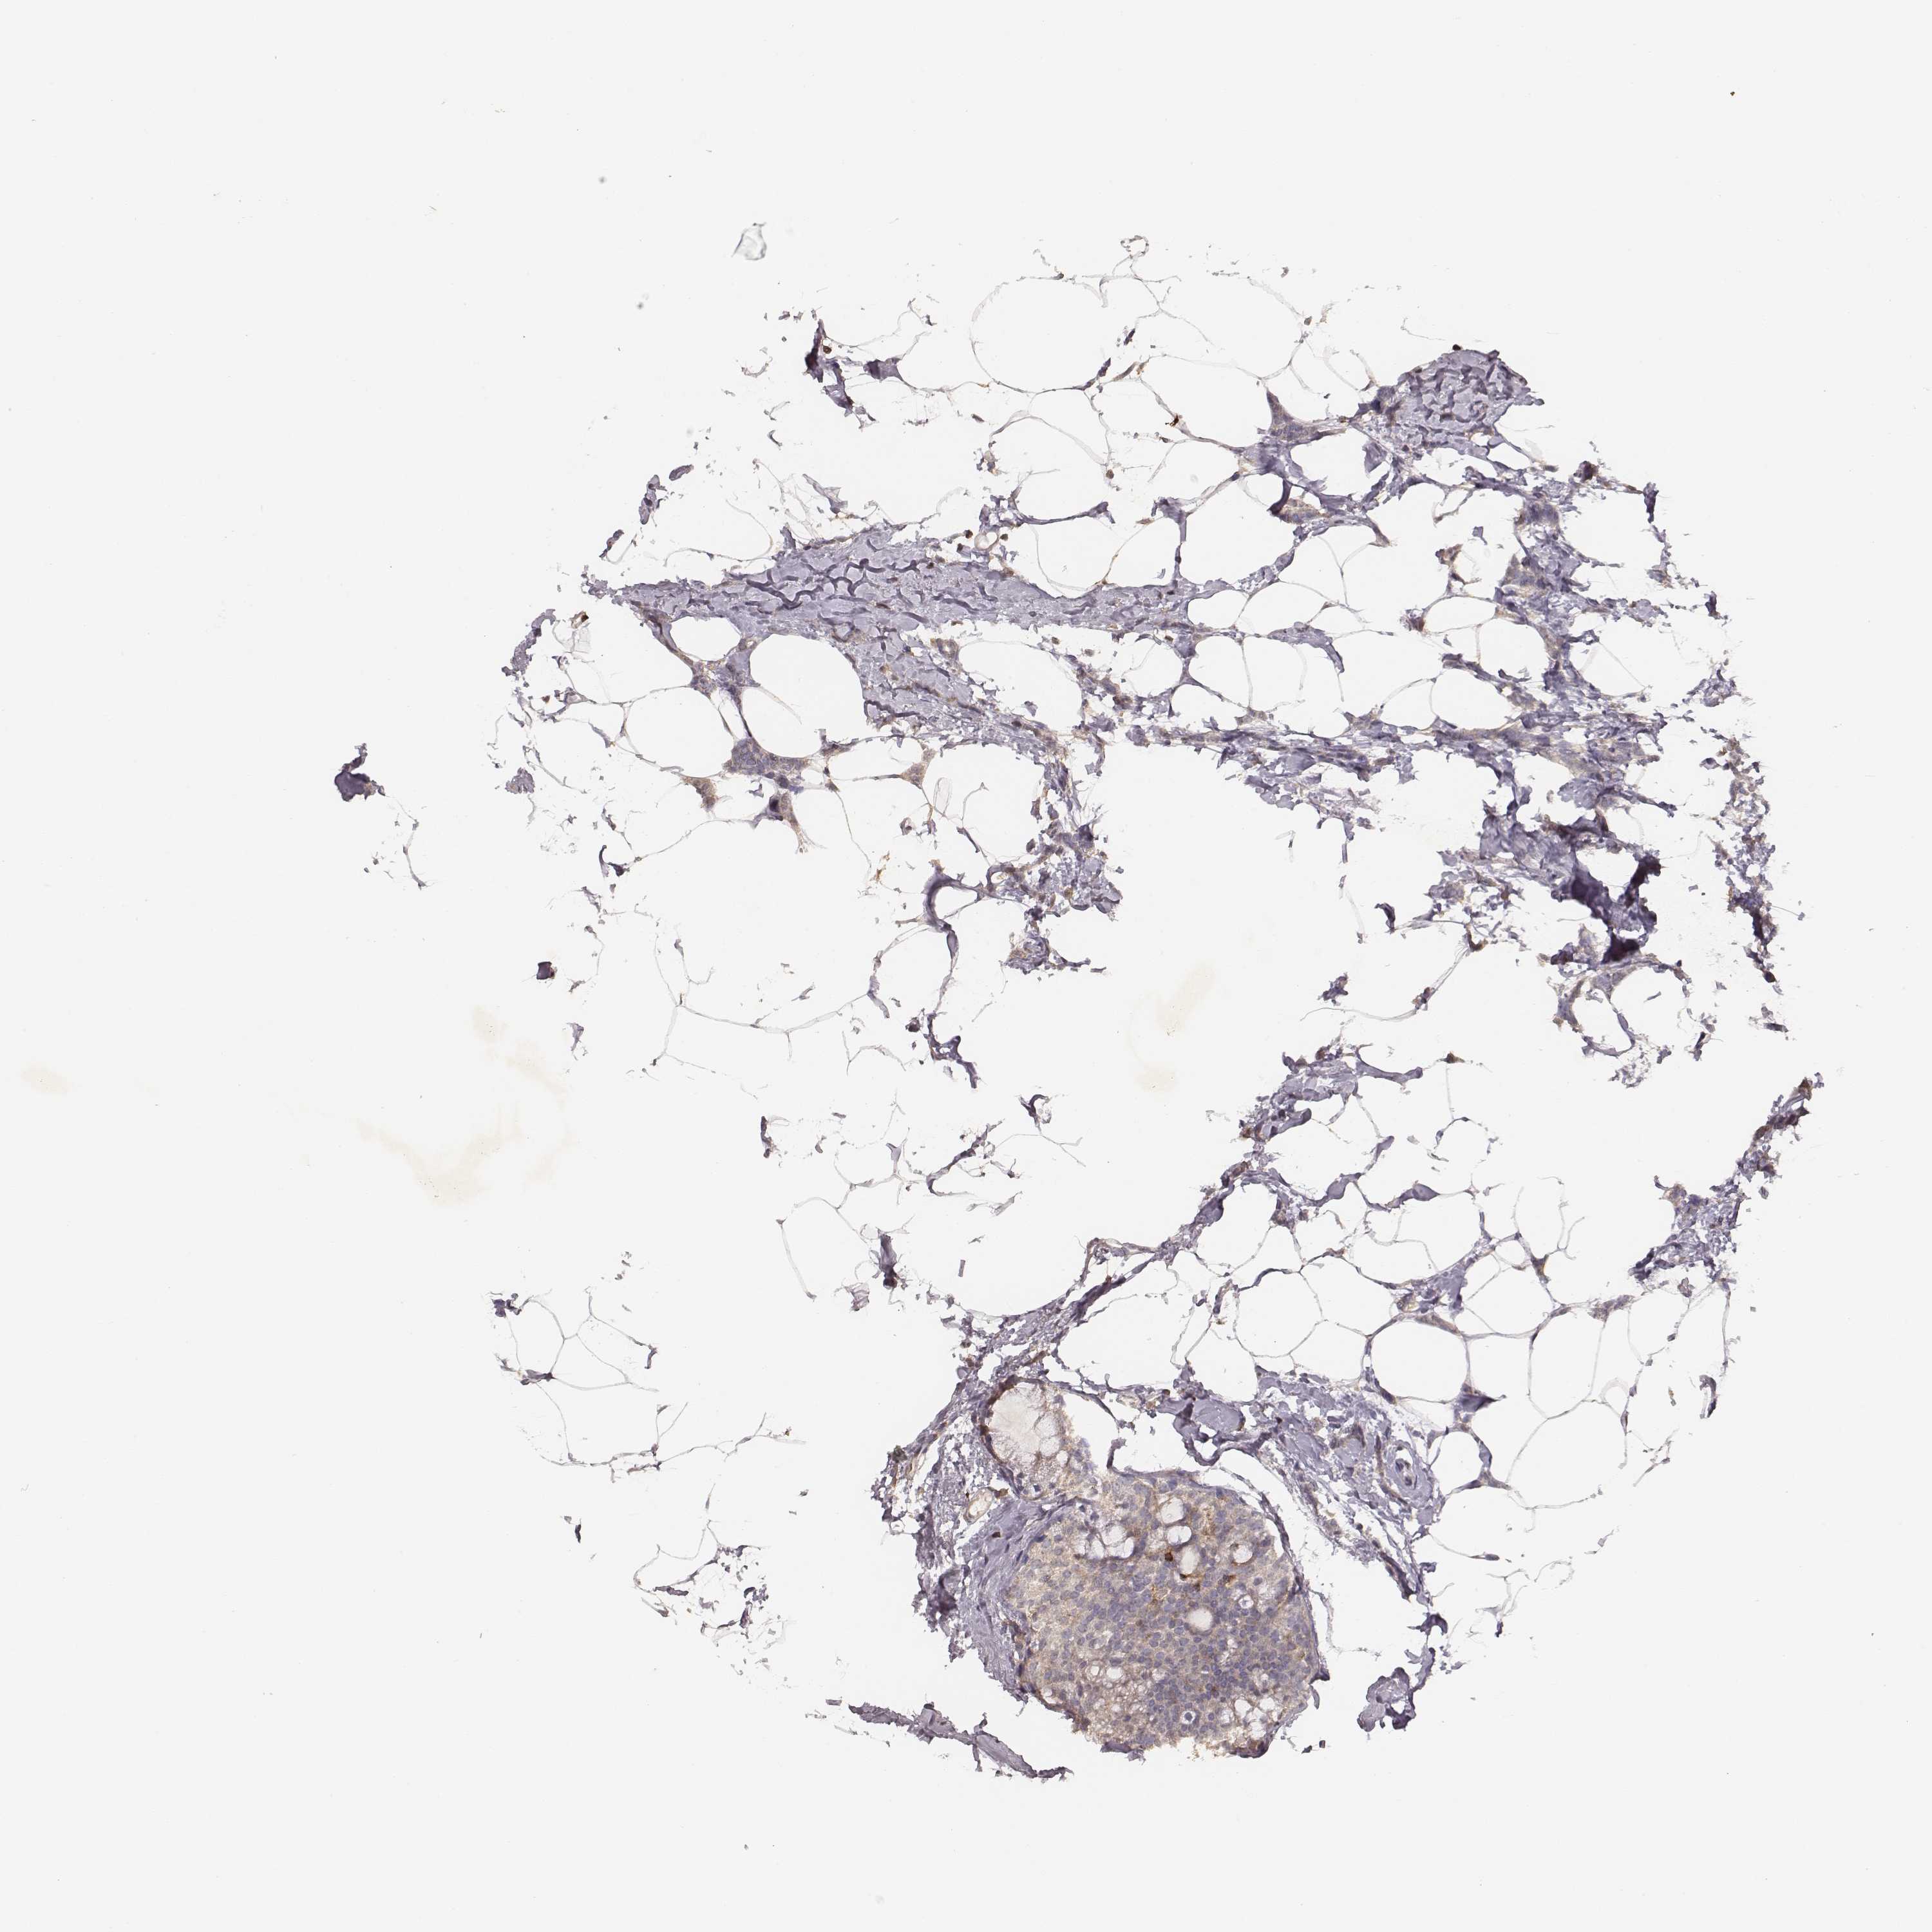

CANCER BREAST CANCER Show tissue menu

Breast cancer

Human cancer